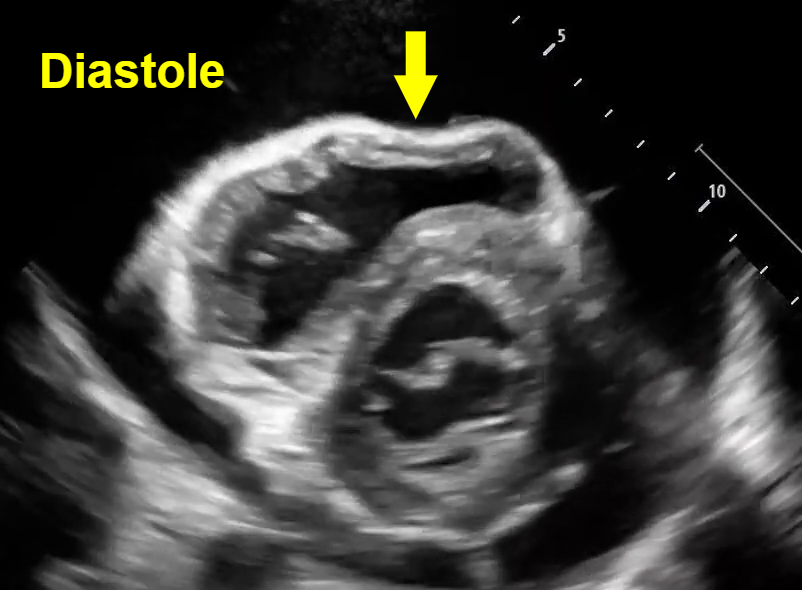

In both parasternal and short axis views seen above, there is a circumferential pericardial effusion surrounding the entire heart.

Parasternal long view: We can see the RV collapse during diastole. How do we know this is diastole? Note that we can see the opening of both the mitral valve and the tricuspid valve to allow for ventricular filling, which occurs during the diastolic phase of cardiac contraction. See clip #1 to see a video of this RV diastolic collapse.

Short axis view: Here we see an example of ‘trampoline sign’, which is the characteristic bouncing motion of the RV. In the image above, we see inversion of the RV wall during diastole (arrow). How do we know this is diastole? Again, note that we can see the opening of the mitral valve in the LV when the RV wall inverts. See clip #2 to see a video of the ‘trampoline sign’.